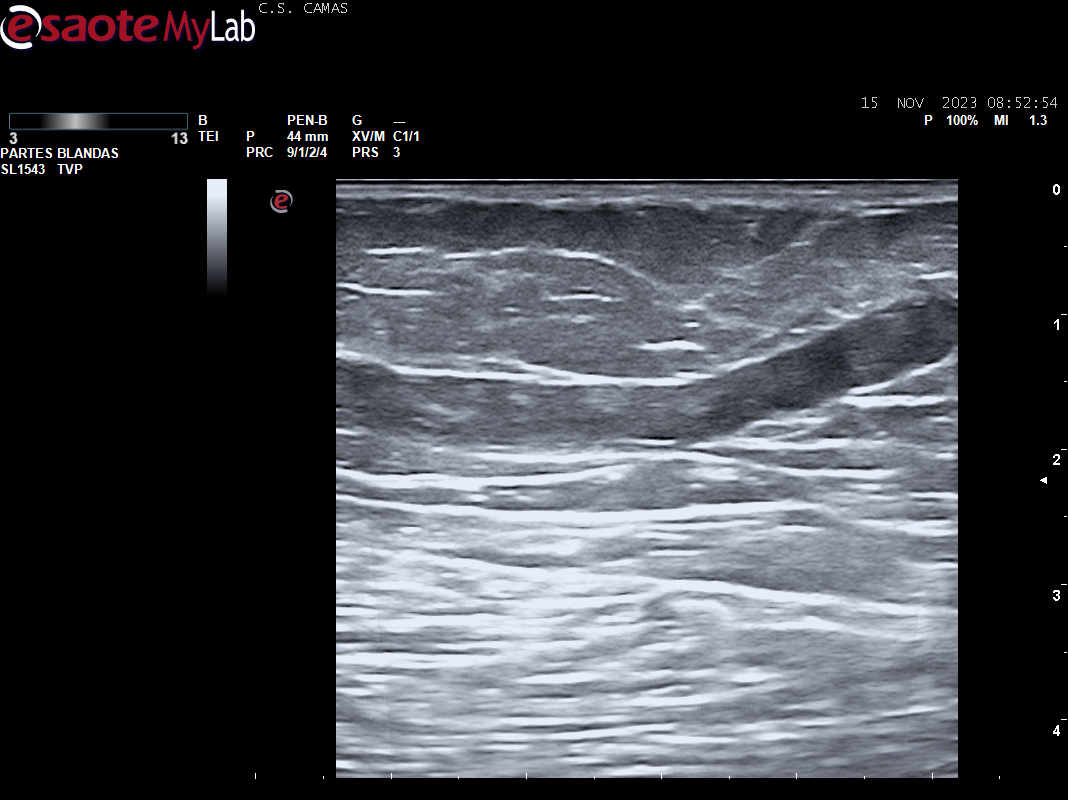

A la exploración se aprecia cordón varicoso en cara interna del muslo izq. Se realiza POCUS en consulta para descartar la presencia de TVP.

Ecografia vascular cara interna del muslo izq: Trombosis de todo el recorrido de la safena izq con dolor al paso de la sonda por colaterales inferiores que colapsan. Presenta además en zona del cayado de la safena imagen heterogenea sin apreciar la llegada de la safena a la femoral común compatible con arrancamiento de la misma.

Trombosis de todo el recorrido de la safena interna izquierda con tromboflebitis de las colaterales inferiores que concuerda con el diagnóstico hospitalario.